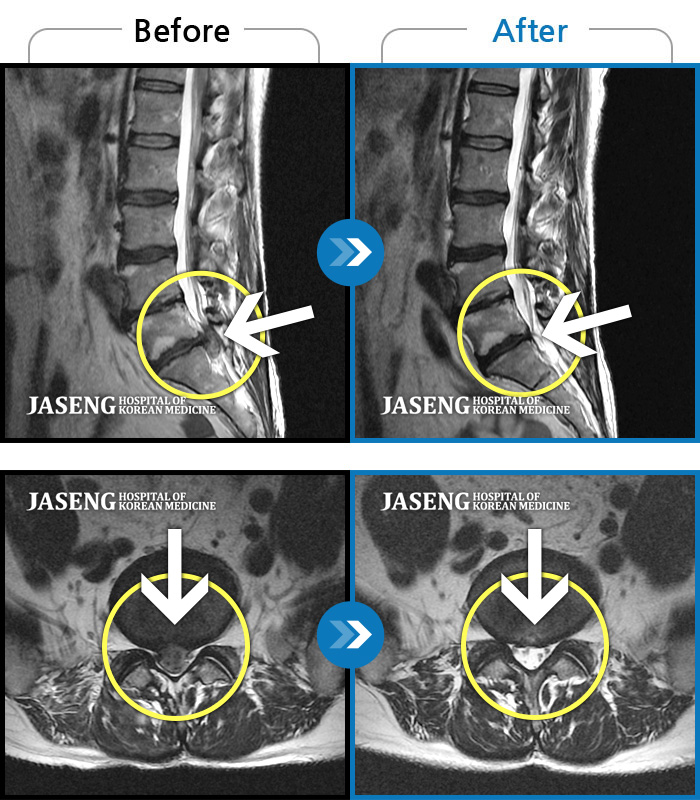

푸쉬업을 여러 번 반복한 뒤 극심한 하요부 통증 및 우측 하지부 저림

2024.03.21 ~ 2024.09.23